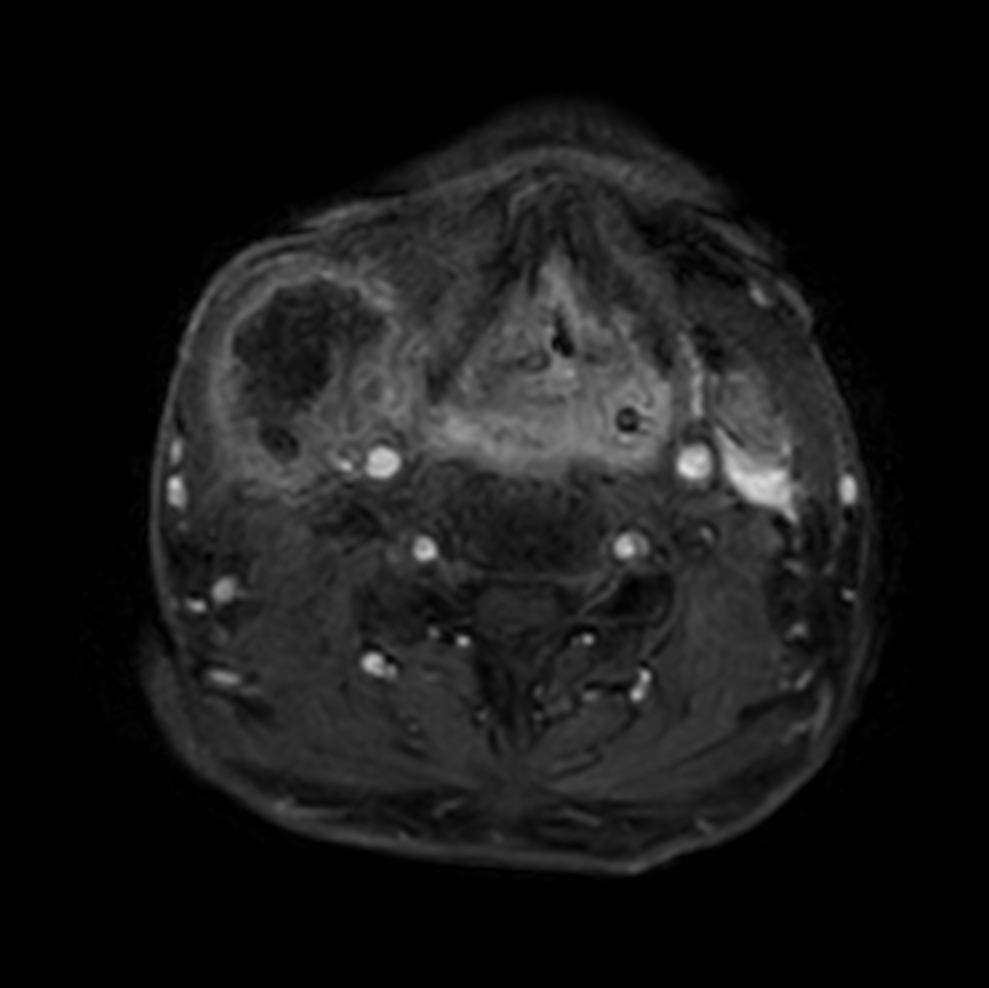

Axial STIR TSE